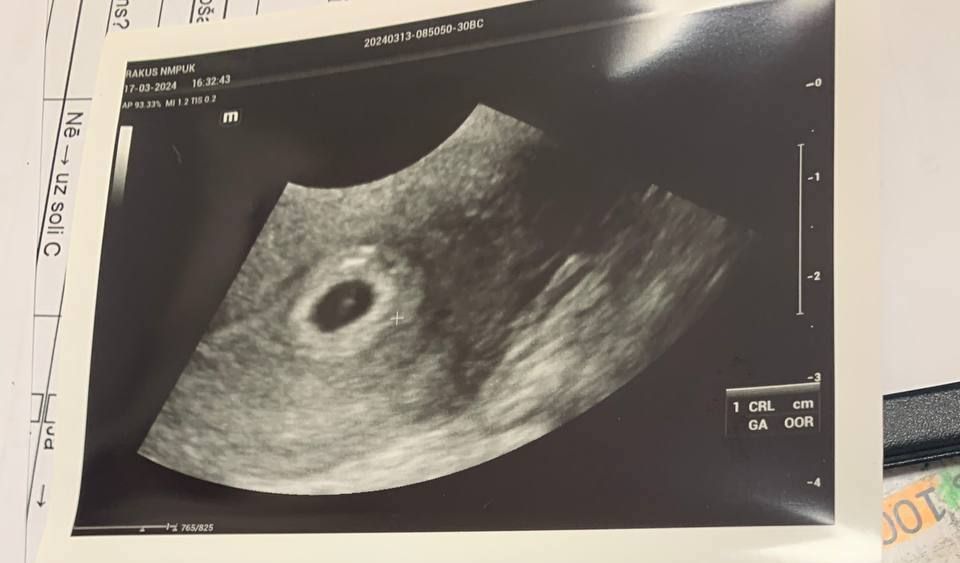

В больнице на УЗИ разглядели небольшую ретрохориальную гематому (отслоение эмбриона от расположенного под ним эндометрия). Назначили Дицинон (3х250 мг в день).

Но есть и хорошие новости: малы со мной и уже стыдливо визуализируется в плодном яйце. Врач говорит, что светящаяся точка в кружочке - это он и есть. Повторное УЗИ через неделю.